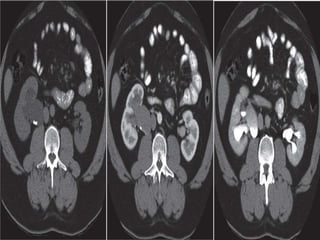

COMPUTED TOMOGRAPHIC SCAN (CT)

- It is an alternative to ultrasonography in the

symptomatic child.

-It is not the preferred modality due to its

radiation exposure.

- In UPJ obstruction, the CT scan typically

shows hydronephrosis without a dilated

ureter.